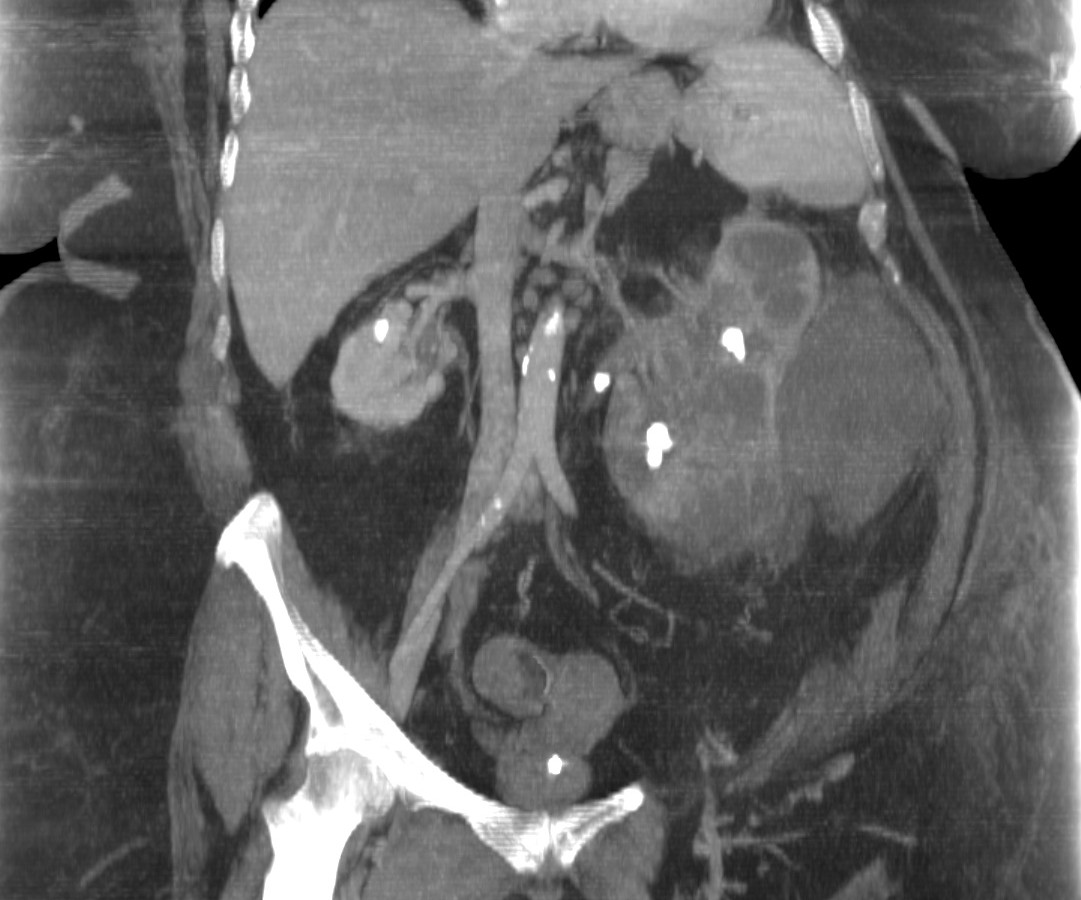

- Aumento difuso del tamaño y pérdida del contorno renal.

- Litiasis coraliforme: cálculo central en pelvis renal contraída (también puede existir calcificaciones intraparenquimatosas). La TC es la mejor técnica para identificar las litiasis.

- Riñón no funcionante (pobre o nula eliminación del medio de contraste en el riñón afectado).

- Cálices renales dilatados (áreas hipodensas) de apariencia multiloculada que se asemeja a una «pata de oso».

- También pueden darse abscesos o áreas de necrosis parenquimatosa.

- Cambios inflamatorios que excede los límites del riñón y genera colecciones periféricas o extensión hacia vísceras vecinas. Pueden darse abscesos en el psoas y fístulas (cutáneas o colónicas) que indican progresión de la enfermedad.

Aunque el área de hipoatenuación que se extiende desde la pelvis renal contraída hasta los cálices renales puede sugerir una hidronefrosis, la baja atenuación corresponde más bien a tejido inflamatorio antes que a líquido (la nefrostomía percutánea no siempre se lleva a cabo).

Paciente mujer de 62 años que acude por decaimiento general con fiebre y dolor en flanco izquierdo. Ingresa en UVI por signos de sepsis

Nos cuenta antecedentes de pielonefritis e hidronefrosis crónica.

Hallazgos en imagen:

Estos hallazgos pueden ser dificiles de interpretar, ya que una paciente con hidronefrosis crónica y litiasis en el uréter puede haber sufrido una obstrucción que origina un cuadro de dolor en FRI con ruptura de cálices y colección extra axial. Otra probabilidad puede ser un angiomiolipoma que ha roto un aneurisma y ha producido un sangrado. También podríamos estar ante una pionefrosis aunque dada dada la clínica, los antecedentes y al observar los hallazgos en TC podríamos establecer la sospecha de pielonefritis xantunogranulomatosa con alta probabilidad. La confrimación vendrá dada con la nefrostomía y estudio de anatomía patológica.